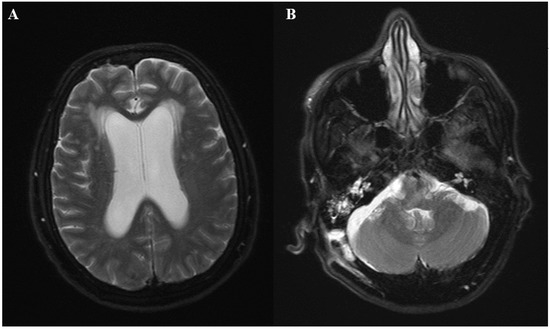

Figure 2.

(A) Histopathology showing fungal elements in hyphal form with acute branching and vague septae (Gomori Methenamine Silver stain, 100×) (B) Positive immunohistochemistry for Aspergillus (Immunostaining, 200×).